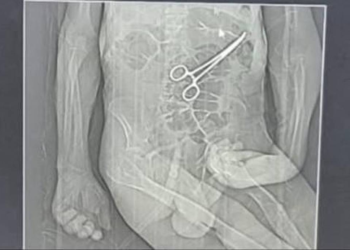

Família acusa hospital de esquecer pinça em corpo de idoso morto na véspera do Natal em MG

Tomografia usada pela família de Manoel Cardoso de Brito para acusar médicos de hospital de João Pinheiro (MG) de deixar...

A família de um aposentado que morreu na véspera do último Natal em João Pinheiro, no noroeste de Minas Gerais, acusa médicos do hospital municipal